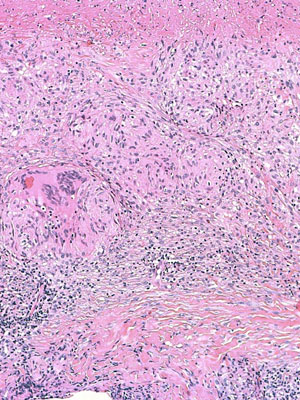

Le diagnostic s’établit sur des images, visualisées au microscope, de prélèvements cellulaires (biopsies, organes ou fragments d’organes, frottis, ponction de liquide).

Afin que les prélèvements soient visualisables au microscope, les techniciens du cabinet de pathologie vont réaliser sur ceux-ci des coupes ultra-fines, secondairement colorées puis mises sur lame de verre.

Le médecin va ensuite visualiser la lame et poser un diagnostic.

Parfois cette analyse nécessite des techniques plus complexes et plus longues, telles que la technique par immunohistochimie et par biologie moléculaire.